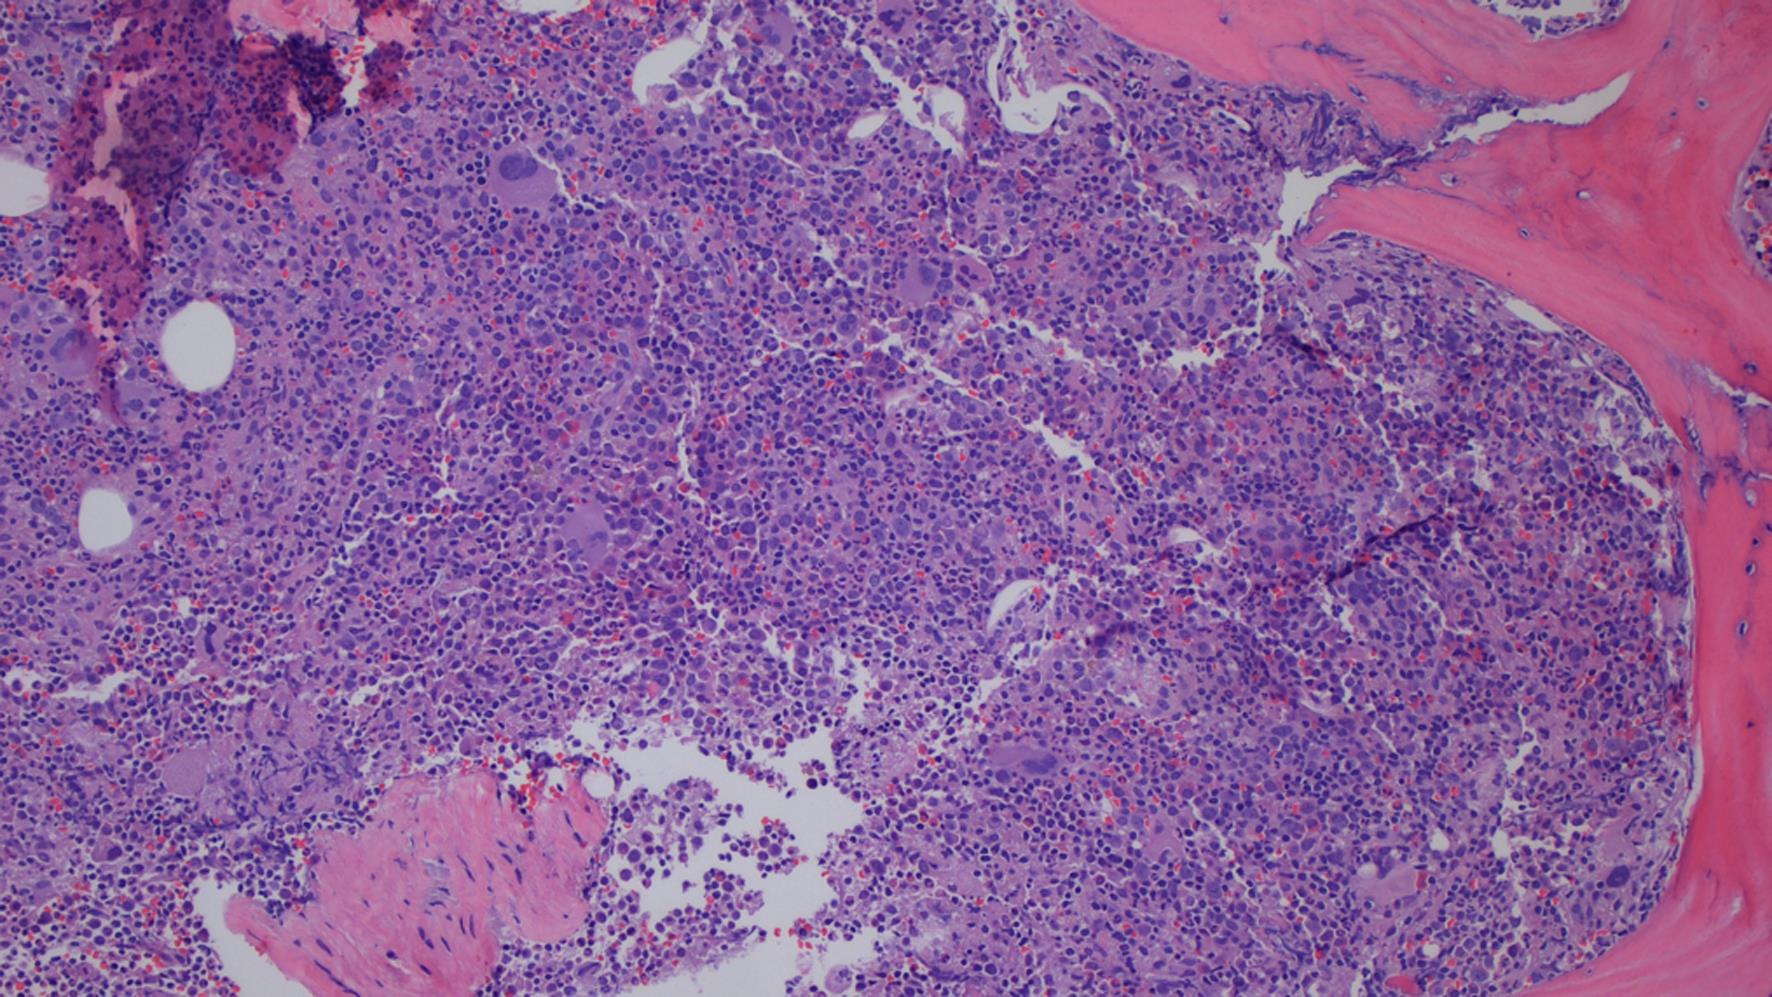

T-LGLL lymphocytes contain small to medium-sized nuclei with condensed chromatin and moderate to abundant pale cytoplasm containing varying amounts of azurophilic granules (Fig. 1). A bone marrow biopsy can be helpful in diagnosing T-LGLL and excluding other causes of cytopenia,26 although the cytological features can sometimes be difficult to appreciate in bone marrow aspirate specimens. Bone marrow biopsy specimens are usually hypercellular (Fig. 2), although normocellular and hypocellular specimens are also seen. Diffuse interstitial lymphoid infiltrates are present in the majority of cases and may be seen concurrently with non-paratrabecular lymphoid nodules. However, the lymphoid infiltrates may be subtle in some cases.27,28

Hypercellular trephine core bone marrow biopsy with lymphoid infiltrate (Hematoxylin and Eosin stain, original magnification 100×).

Fig. 2  Hypercellular trephine core bone marrow biopsy with lymphoid infiltrate (Hematoxylin and Eosin stain, original magnification 100×).